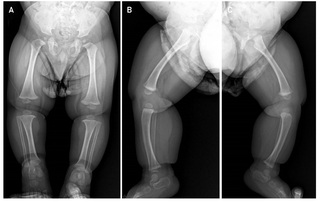

Se trata de infante masculino de 2 años, primer hijo de padres no consanguíneos, sin antecedentes relevantes del embarazo y del parto a término y sin complicaciones, quien es referido a la consulta de Genética por su médico pediatra por talla baja severa (- 5DS), y con un proceso de sospecha diagnóstica en curso de una displasia esquelética. El paciente tiene dos medios hermanos paternos (Figura 1). Al examen físico el paciente presentaba hallazgos dismorfológicos leves que incluían hipoplasia de la parte media de la cara, puente nasal plano, macrocefalia relativa, protuberancia frontal, braquidactilia y lordosis (Figura 2). Evaluaciones radiográficas a los 11 meses de todo el esqueleto revelaron como único hallazgo notable ensanchamiento en copa de ambos fémures con discreto acortamiento longitudinal de ambas tibias con curvatura anteroposterior sugerente de displasia ósea (Figura 3), y con un estudio edad ósea, que revelaba una edad ósea avanzada para la edad de 1 año y 3 meses (4 meses). El paciente recibió estimulación temprana por haberse detectado un ligero retraso del desarrollo psicomotor con hipertonía y al año ya cumplía con todos los hitos del desarrollo. En el proceso de evaluación se realizaron pruebas genéticas moleculares.

En nuestro caso, se detectó una variante probablemente patogénica (variante clase 2) en el gen ACAN no descrita previamente, que origina un codón de parada prematuro, el cual resulta en una degradación mediada sin sentido (Nonsense-mediated-degradation or NMD) del mARN del alelo mutante y, por lo tanto, se presume una haploinsuficiencia para el agrecano [14]. Las manifestaciones clínicas de nuestro paciente, aparte de la talla baja de - 5 DS, principal causa de consulta y preocupación, son relativamente leves, siendo lo más llamativo una frente ligeramente prominente y las extremidades inferiores ligeramente en varo (Figura 2).